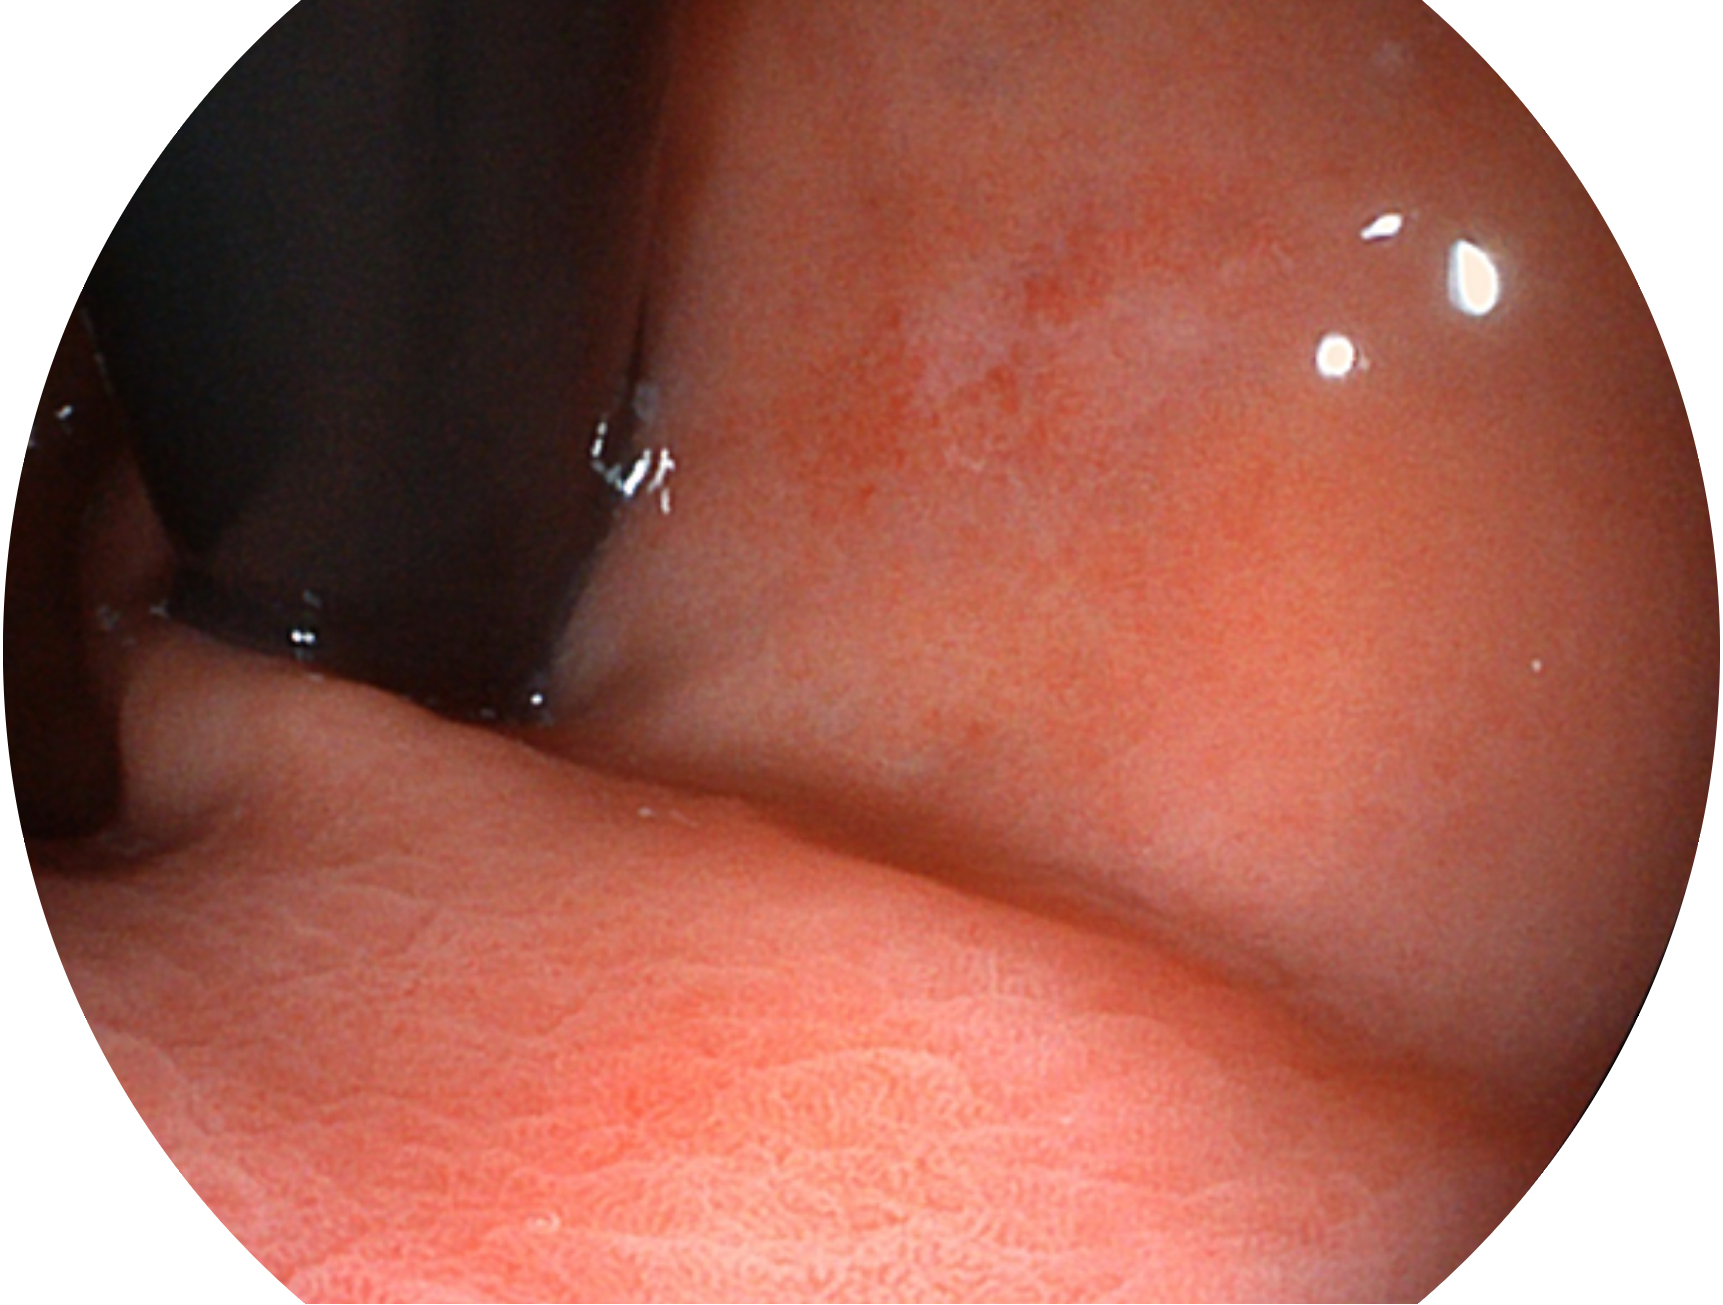

开立新开发的内镜染色技术,主要是基于多波长LED 光源的开发,VLS-55Q 四波长LED 光源是由四个不同颜色的LED光按照相应照明模式所规定的特定发光比例进行合束后形成,合束后形成的照明光的光谱由红光、绿光、蓝光及蓝紫光这四个不同的波段范围构成。具有更高光谱自由度,通过光谱比例的控制,实现了聚谱成像技术,英文全称为“Spectral Focused Imaging, SFI”,缩写为“SFI”和光电复合染色成像技术,英文全称为“Versatile Intelligent Staining Technology, VIST”,缩写为“VIST”。